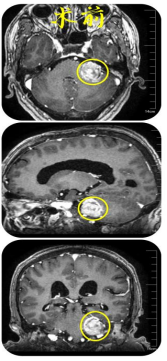

术前,核磁共振检查提示,患者左侧桥小脑角占位。

术中,在显微镜辅助下配合神经电生理监测,团队仔细辨别面、听神经,小心沿包膜分离面、听神经和肿瘤,经过数小时的紧张操作,成功地将肿瘤完整切除。